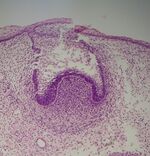

Histologic slide showing a tooth bud.